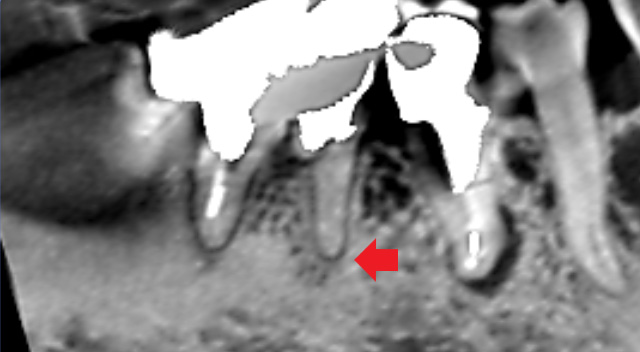

下の画像は、根管治療されていた大臼歯の初診時のCT画像です。根の先には根尖病変の炎症像は特にみられませんでした。他の歯の治療後の経過観察中に膿ができてきたケースです。根管治療が必要になったので、通法通り再根管治療を行い、膿は改善しました。